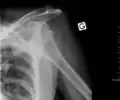

X-ray at left shows anterior dislocation in a young man. X-ray at right shows the same shoulder after reduction and internal rotation, revealing a Bankart lesion and a Hill-Sachs lesion.

In over 95% of shoulder dislocations, the humerus is displaced anteriorly.[8] In most of those, the head of the humerus comes to rest under the coracoid process, referred to as sub-coracoid dislocation. Sub-glenoid, subclavicular, and, very rarely, intrathoracic or retroperitoneal dislocations may also occur.[9]

A Hill–Sachs lesion is an impaction of the head of the humerus left by the glenoid rim during dislocation.[6] Hill-Sachs deformities occur in 35–40% of anterior dislocations. They can be seen on a front-facing X-ray when the arm is in internal rotation.[11] Bankart lesions are disruptions of the glenoid labrum with or without an avulsion of bone fragment.[12]